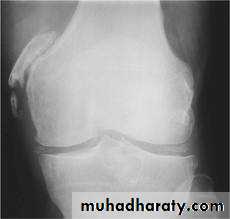

ARTICULAR DISORDERS OF THE KNEE

ARTHRITISPyogenic arthritis

Rheumatoid arthritis

Tuberculous arthritis

Osteoarthritis

Haemophilic arthritis

Neuropathic arthritis

Chondromalacia of the patella